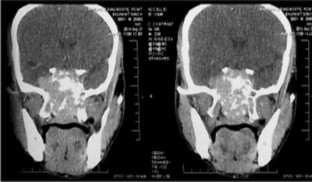

Primary localized amyloidosis in the head and neck region is a rare entity. The most commonly involved organ is larynx. Primary amyloidosis localized to the sinonasal tract is extremely rare. We report one such case along with a brief review of the associated literature. The aim of reporting this case is to emphasize the fact that sometimes nasal amyloidosis can also present with signs and symptoms of nasal and nasopharyngeal malignancy. The definitive diagnosis in such cases depends upon histopathology and further confirmed by immunohistochemistry. A 55-year old male presented with recurrent episodes of nasal bleed, bilateral nasal obstruction, and bilateral hearing loss from last 7 years. On clinical examination a mass was found in the nasal cavity on both sides reaching up to the nasopharynx. Contrast enhanced CT scan revealed that the mass was extending up to the skull base and destroying bony landmarks of the nasal cavity and paranasal sinuses. Mass was proved to be amyloidosis after histopathological examination. It showed multiple blotches of globular submucosal deposit of amyloid, on staining with Congo red. Immunohistochemistry confirmed AL amyloidosis with expression of mixed kappa and lambda light chain immunoglobulin (κ > λ). No evidence of systemic amyloidosis was found after proper work up. It was managed by conservative surgery.